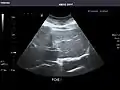

Aorta: Visualized portions normal in caliber, 16 x 15 mm.

Aorta